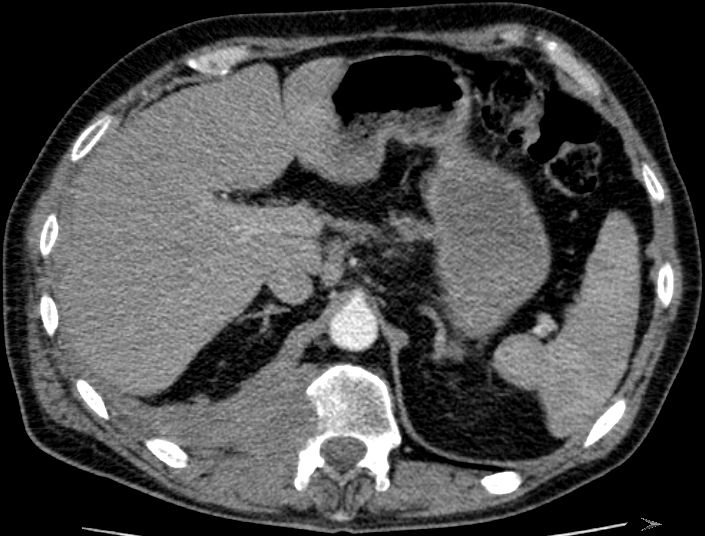

| Hüftpfanne | 74-jähriger Mann mit einem Adenokarzinom des rechten Lungenoberlappens pT1b pN2 Mo 1 Jahr nach Lobektomie Bestrahlung und

Chemotherapie. Die dorsalen Hüftpfannenteile links und Teile des Sitzbeins sind völlig zerstört.![]() |

Nach einem Sturz hat sich zusätzlich ein Haematom gebildet und der linke Hüftkopf hat sich nach dorsal verlagert.![]() |